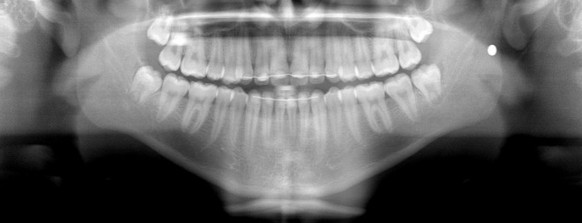

Doch in den darauffolgenden Tagen nehmen die Schmerzen im Kiefer zu. Sein Zahnfleisch entzündet sich. Jasper geht zum Zahnarzt. Dieser macht ein Röntgenbild und stellt fest: Seine Weisheitszähne müssten gezogen werden.

Der Zahnarzt zieht ihm noch am selben Tag einen seiner Weisheitszähne – ohne dabei die Kugel zu entdecken.

Eine Woche später muss Jasper erneut zum Zahnarzt, um die Fäden zu ziehen. Seine Mutter begleitet ihn. Als der Zahnarzt ihr das Röntgenbild zeigt, um zu erklären, dass er auch die anderen Weisheitszähne ihres Sohnes ziehen müsse, sticht ihr etwas ganz anderes ins Auge. Ein weisser Punkt.

«Ich habe sofort gefragt, was das ist. Er riss seine Augen weit auf und sagte, es sei etwas, dass da nicht hingehöre», erinnert sich Jaspers Mutter Sandra im Gespräch mit watson. Sie hat die Kugel in Jaspers Kiefer entdeckt.